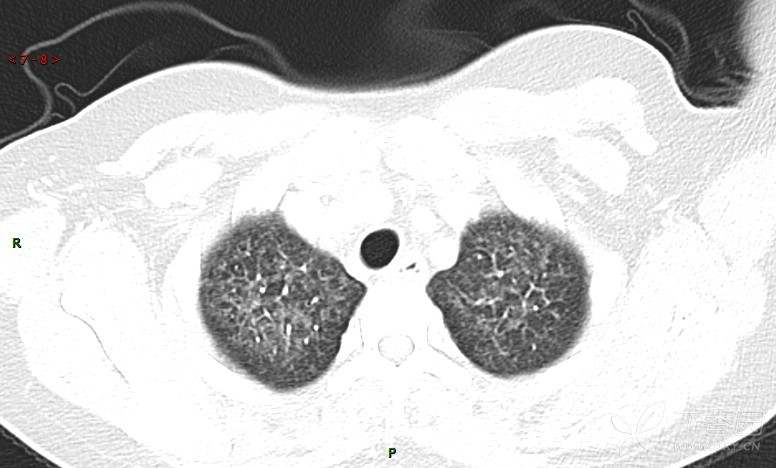

肺内弥漫性网状结节影,PET-CT却无阳性病灶,这是?(附其他2例链接)

女性,58岁,阵发性咳嗽2月,加重1月。

患者于2月前无明显诱因出现咳嗽,以阵发性干咳为主,接触冷空气后咳嗽明显,偶咳少量白色泡沫样痰,咳嗽剧烈时感憋喘,无发热、盗汗,无头痛、头晕,无胸痛、咯血,无恶心、呕吐,无腹痛、腹泻,无尿频、尿痛等不适,于当地医院给予肌注及静脉药物治疗,具体药物名称不详,效果欠佳,近1月来患者咳嗽频率较前增加,咳嗽剧烈时感双侧季肋区疼痛不适,10余天前出现发热,体温在38℃左右,伴畏寒、寒战,无头痛、头晕,无纳差、乏力等不适,药物治疗后体温降至正常,仍阵发性咳嗽,今为求进一步诊治,就诊于我院急诊,因呼吸内科暂无床位,急诊门诊以“肺间质病变”收入急诊留观室,给予“抗感染、止咳”等对症支持治疗后,今日以“肺间质性病变”收入我科,患者自本次发病以来,神志清,精神可,饮食尚可,睡眠一般,大小便正常,体重较前无明显变化。

患者活检肺组织后行PET/CT检查